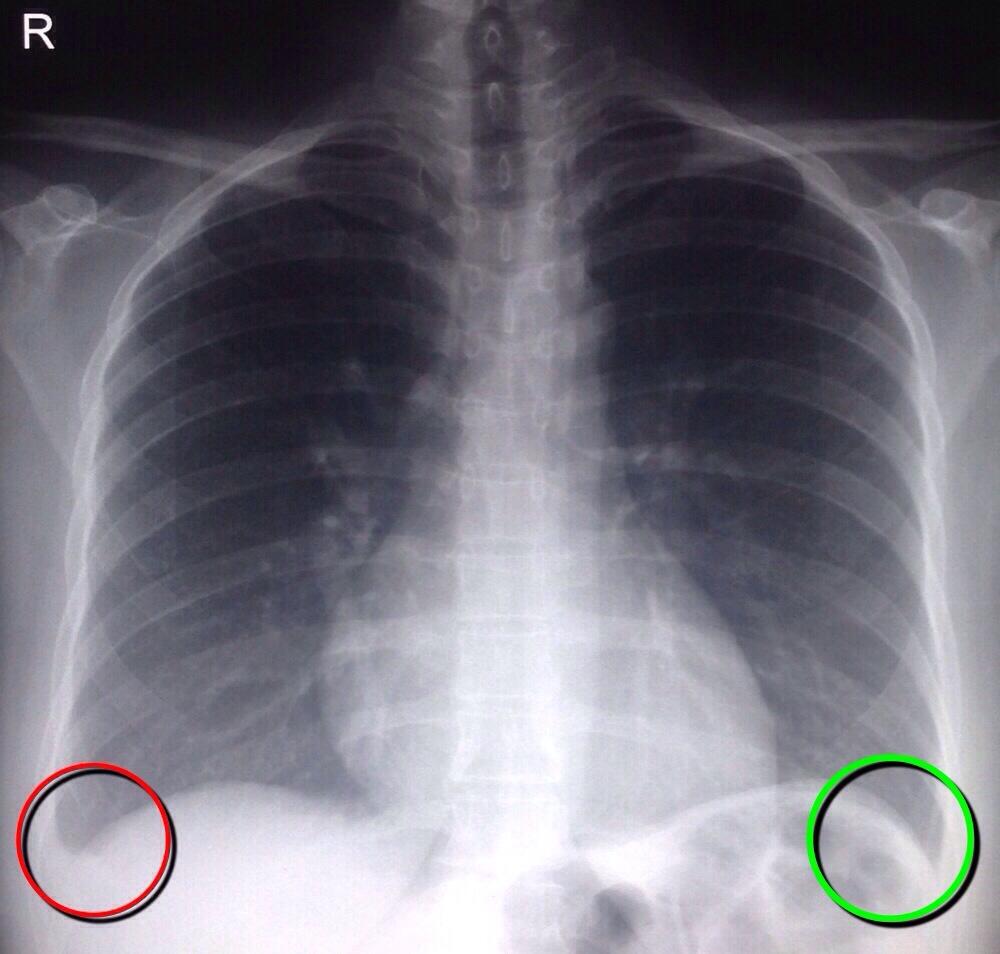

(A) CXR revealed basal opacity with obliterated costophrenic angle (red X Ray Costophrenic Angle Blunting of the costophrenic angles is usually caused by a pleural effusion, as already discussed. The costophrenic angle is abnormally deepened when the pleural air collects laterally, producing the deep sulcus sign. The costophrenic angles are formed by the points at which the chest wall and diaphragm meet. It represents lucency of the lateral costophrenic angle extending toward the hypochondrium. X Ray Costophrenic Angle.

X Ray Costophrenic Angle . The costophrenic angles are formed by the points at which the chest wall and diaphragm meet. It represents lucency of the lateral costophrenic angle extending toward the hypochondrium (figure). The costophrenic angle is abnormally deepened when the pleural air collects laterally, producing the deep sulcus sign. The angle is observed as a downward indentation between the left or right diaphragm and adjacent. Blunting of the costophrenic angles is usually caused by a pleural effusion, as already discussed. Other causes of costophrenic angle blunting include lung. The costophrenic angles are limited views of the costophrenic recess. On a frontal view the costophrenic angles should be sharp. The image is of a patient in the icu who is on.